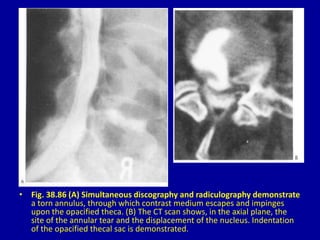

• Fig. 38.86 (A) Simultaneous discography and radiculography demonstrate

a torn annulus, through which contrast medium escapes and impinges

upon the opacified theca. (B) The CT scan shows, in the axial plane, the

site of the annular tear and the displacement of the nucleus. Indentation

of the opacified thecal sac is demonstrated.

• Fig. 38.86(A) Simultaneous discography and radiculography demonstrate a torn annulus, through which contrast medium escapes and impinges upon the opacified theca. (B) The CT scan shows, in the axial plane, the site of the annular tear and the displacement of the nucleus. Indentation of the opacified thecal sac is demonstrated.